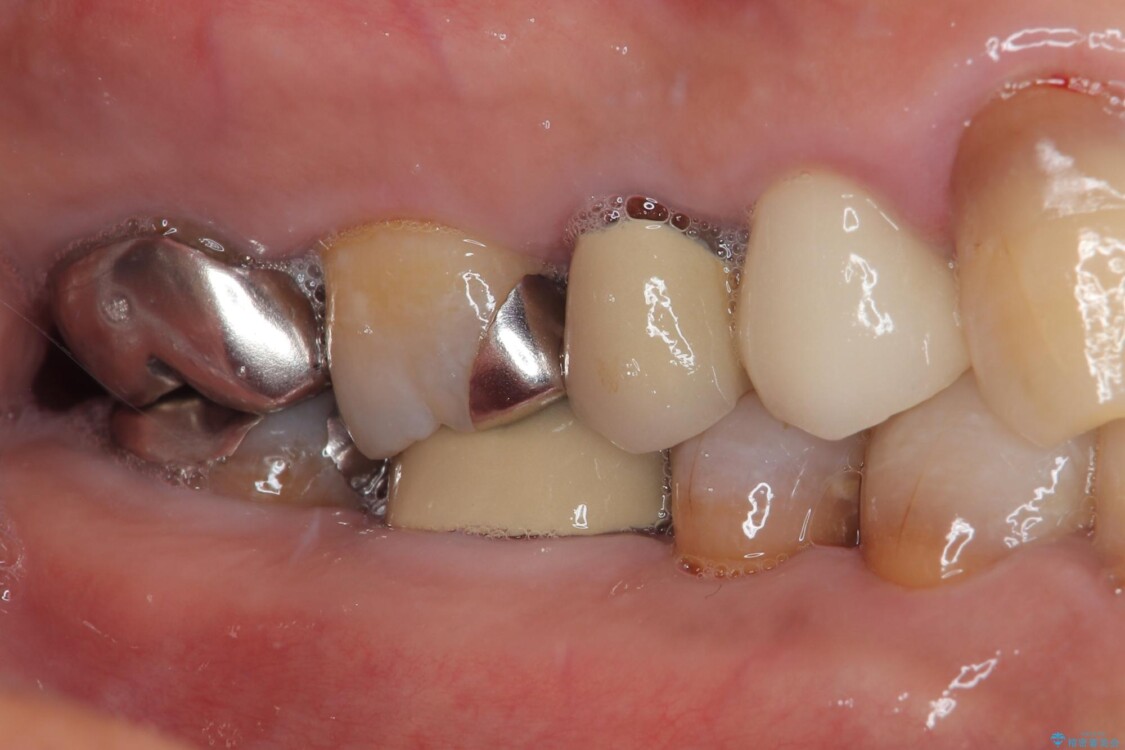

ファイバーコアを築造・精密な支台歯形成と印象採得

オールセラミッククラウンの装着

治療途中

• 自然な美しさと強度を両立!右上小臼歯の被せもの脱離に対する審美補綴治療 治療前画像